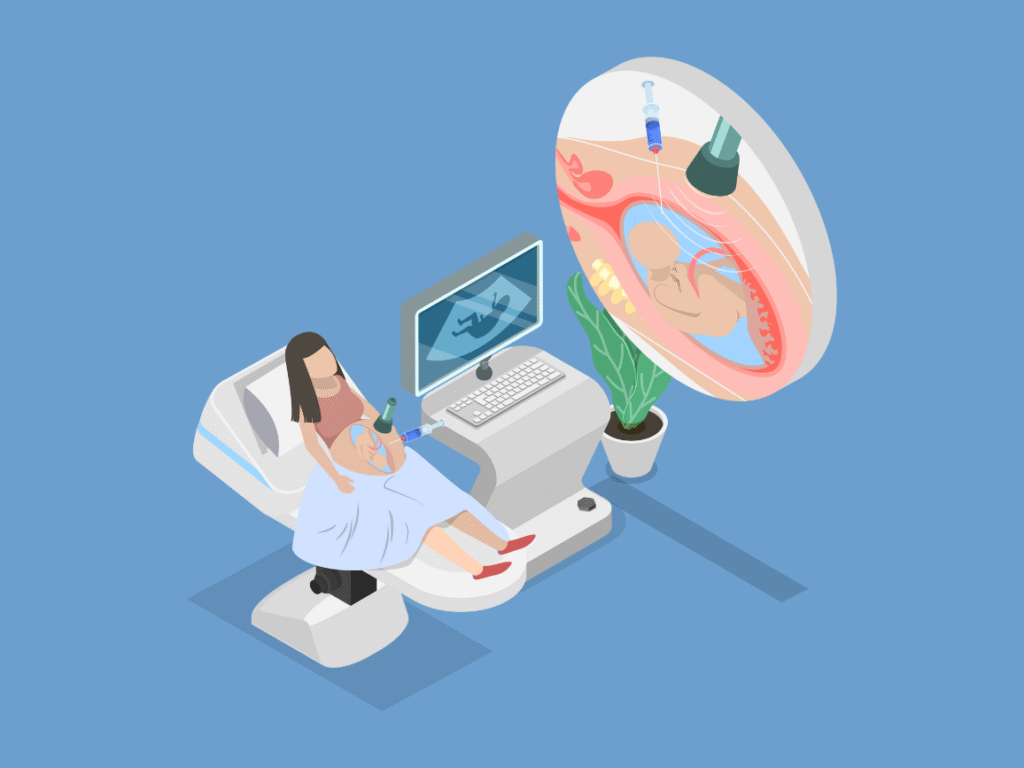

If you’re looking for advanced fetal diagnosis in Kolkata, visit NESA Istitute of Fetal Medicine — a centre equipped with state-of-the-art ultrasound technology and specialized fetal medicine experts. At NESA, your Fetal care will be handled by a team of Skilled Fetal medicine Team under the guidance and supervision of Dr Khurshid Alam, a nationally acclaimed Maternal Fetal Medicine specialist.

At advanced fetal diagnostic centres, all procedures are done using sterile techniques, real-time imaging, and gentle precision. Patients receive pre-procedure counselling, continuous monitoring, and follow-up support to ensure a safe and stress-free experience.

Your Care Journey at NESA

Counselling → Diagnostic → Intervention → Support

- Counselling: Every patient begins with a detailed discussion with a fetal medicine expert to understand the available testing options.

- Diagnostic: Based on the findings and clinical history, appropriate tests such as ultrasound, amniocentesis, or CVS are recommended.

- Intervention: If a treatable fetal condition is detected, the care team provides advanced in-utero therapy or supportive management.

- Support: Continuous emotional, genetic, and medical support is offered to guide families through every stage of pregnancy.